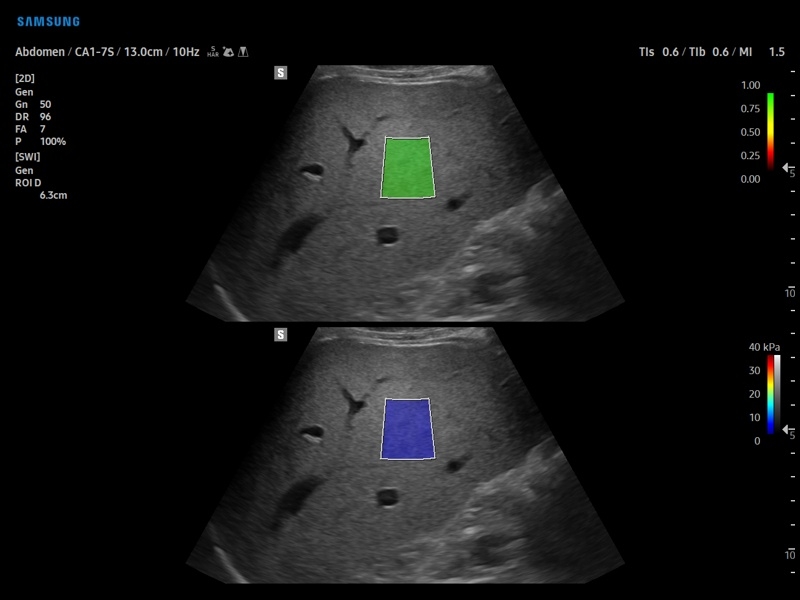

• S-Shearwave Imaging для эластографии сдвиговой волной

• Модуль S-Shearwave imaging – программа цветовой сдвиговой эластографии позволяющая автоматически определять индекс жесткости различных участков исследуемого объекта в кПа или м/с, получая при это еще и индекс достоверности данных RMI.